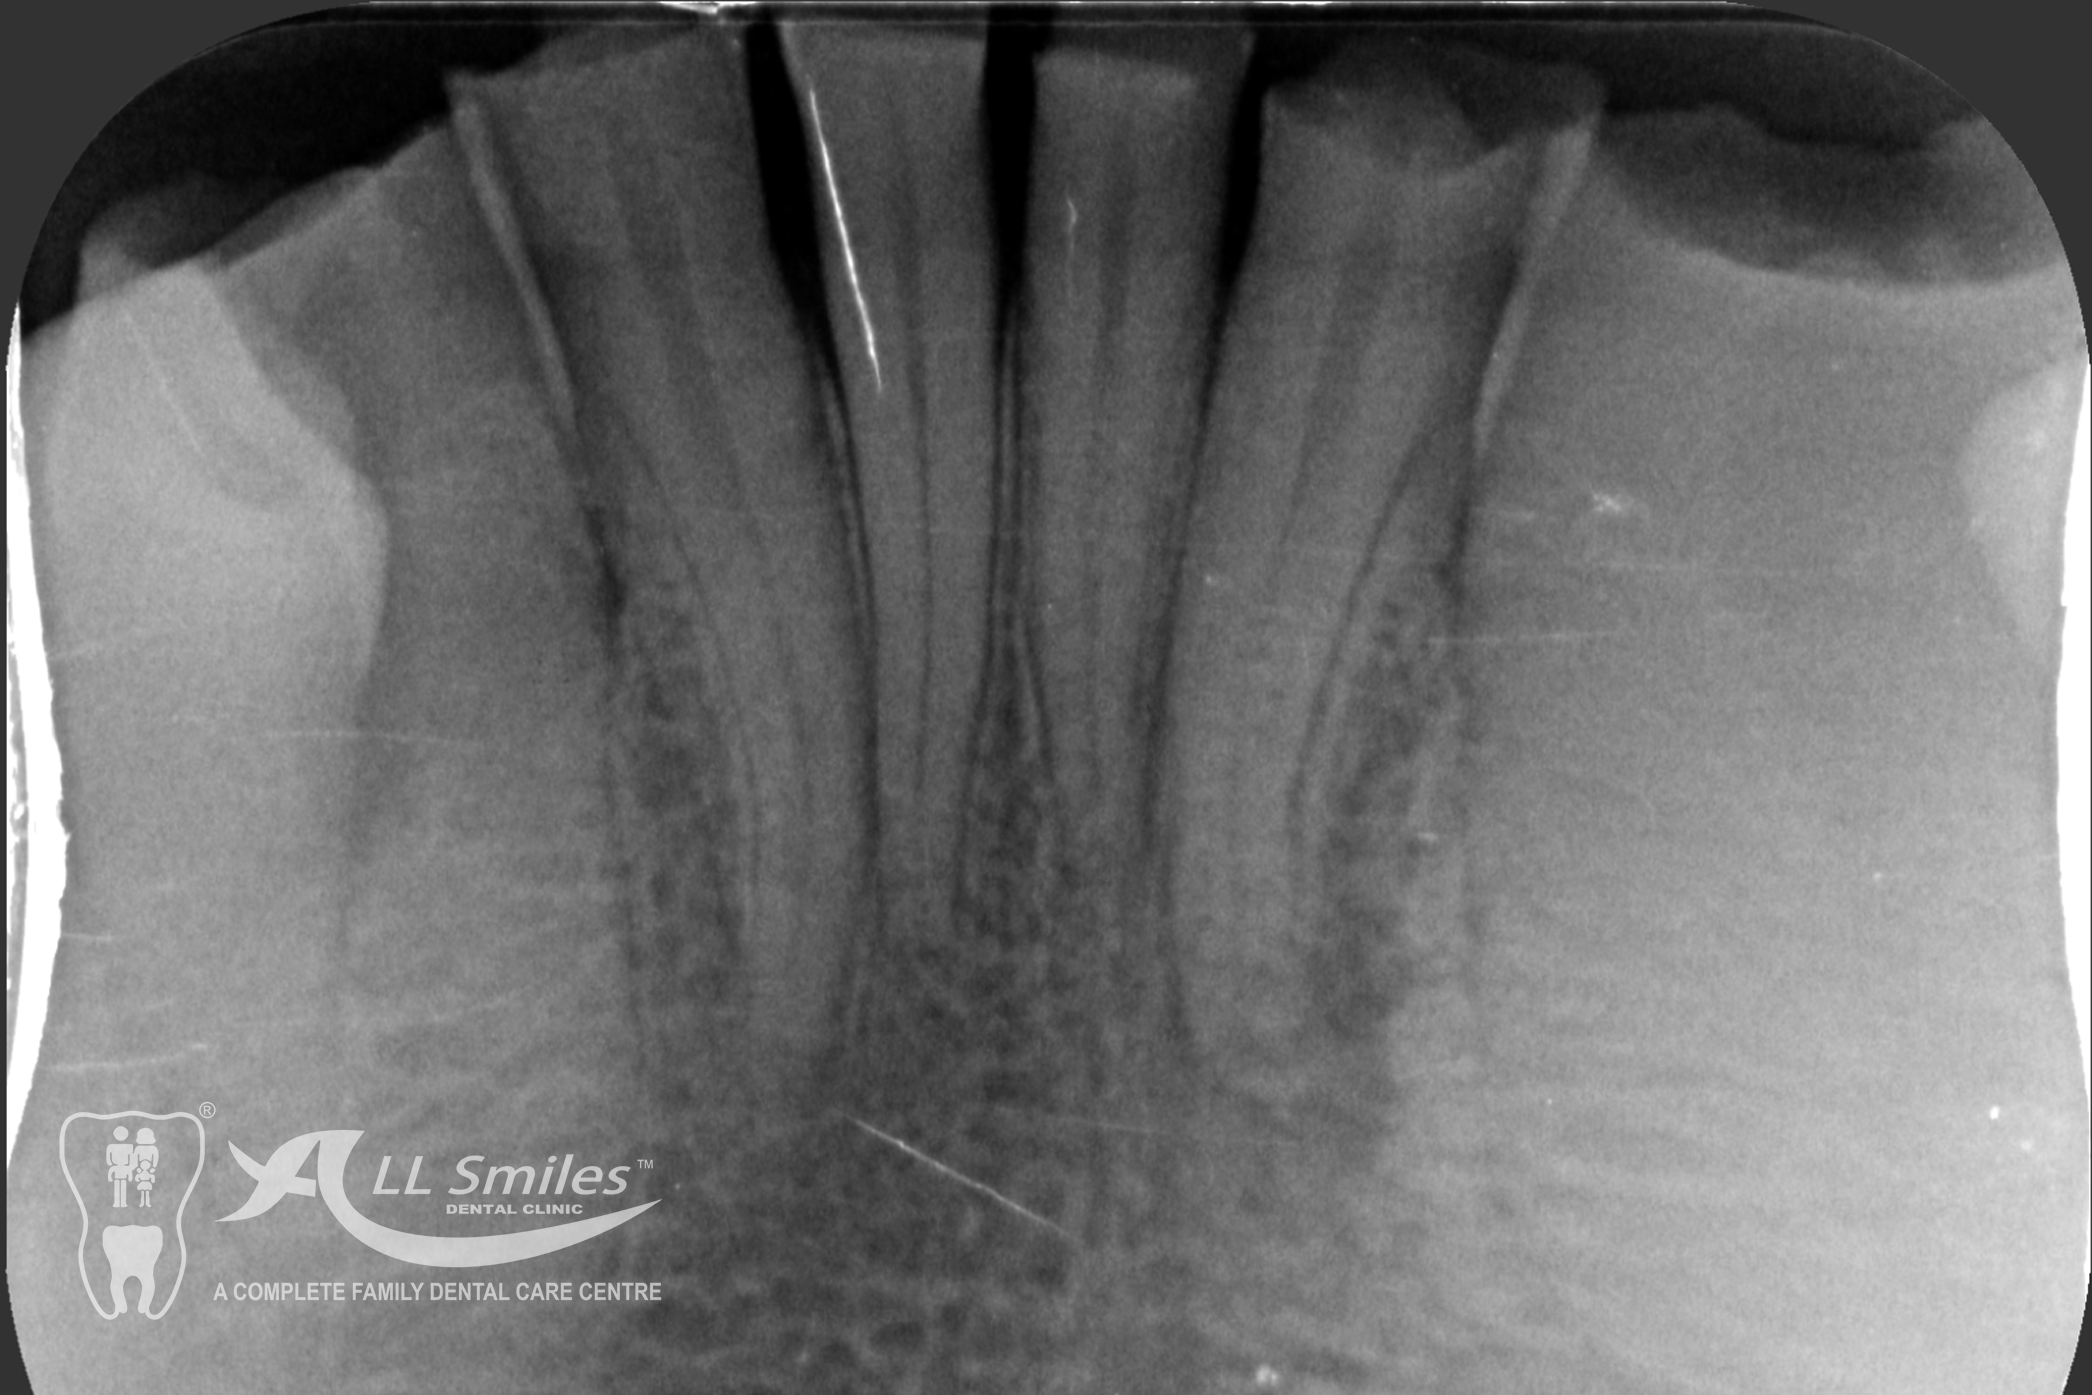

Root Canal Gallery